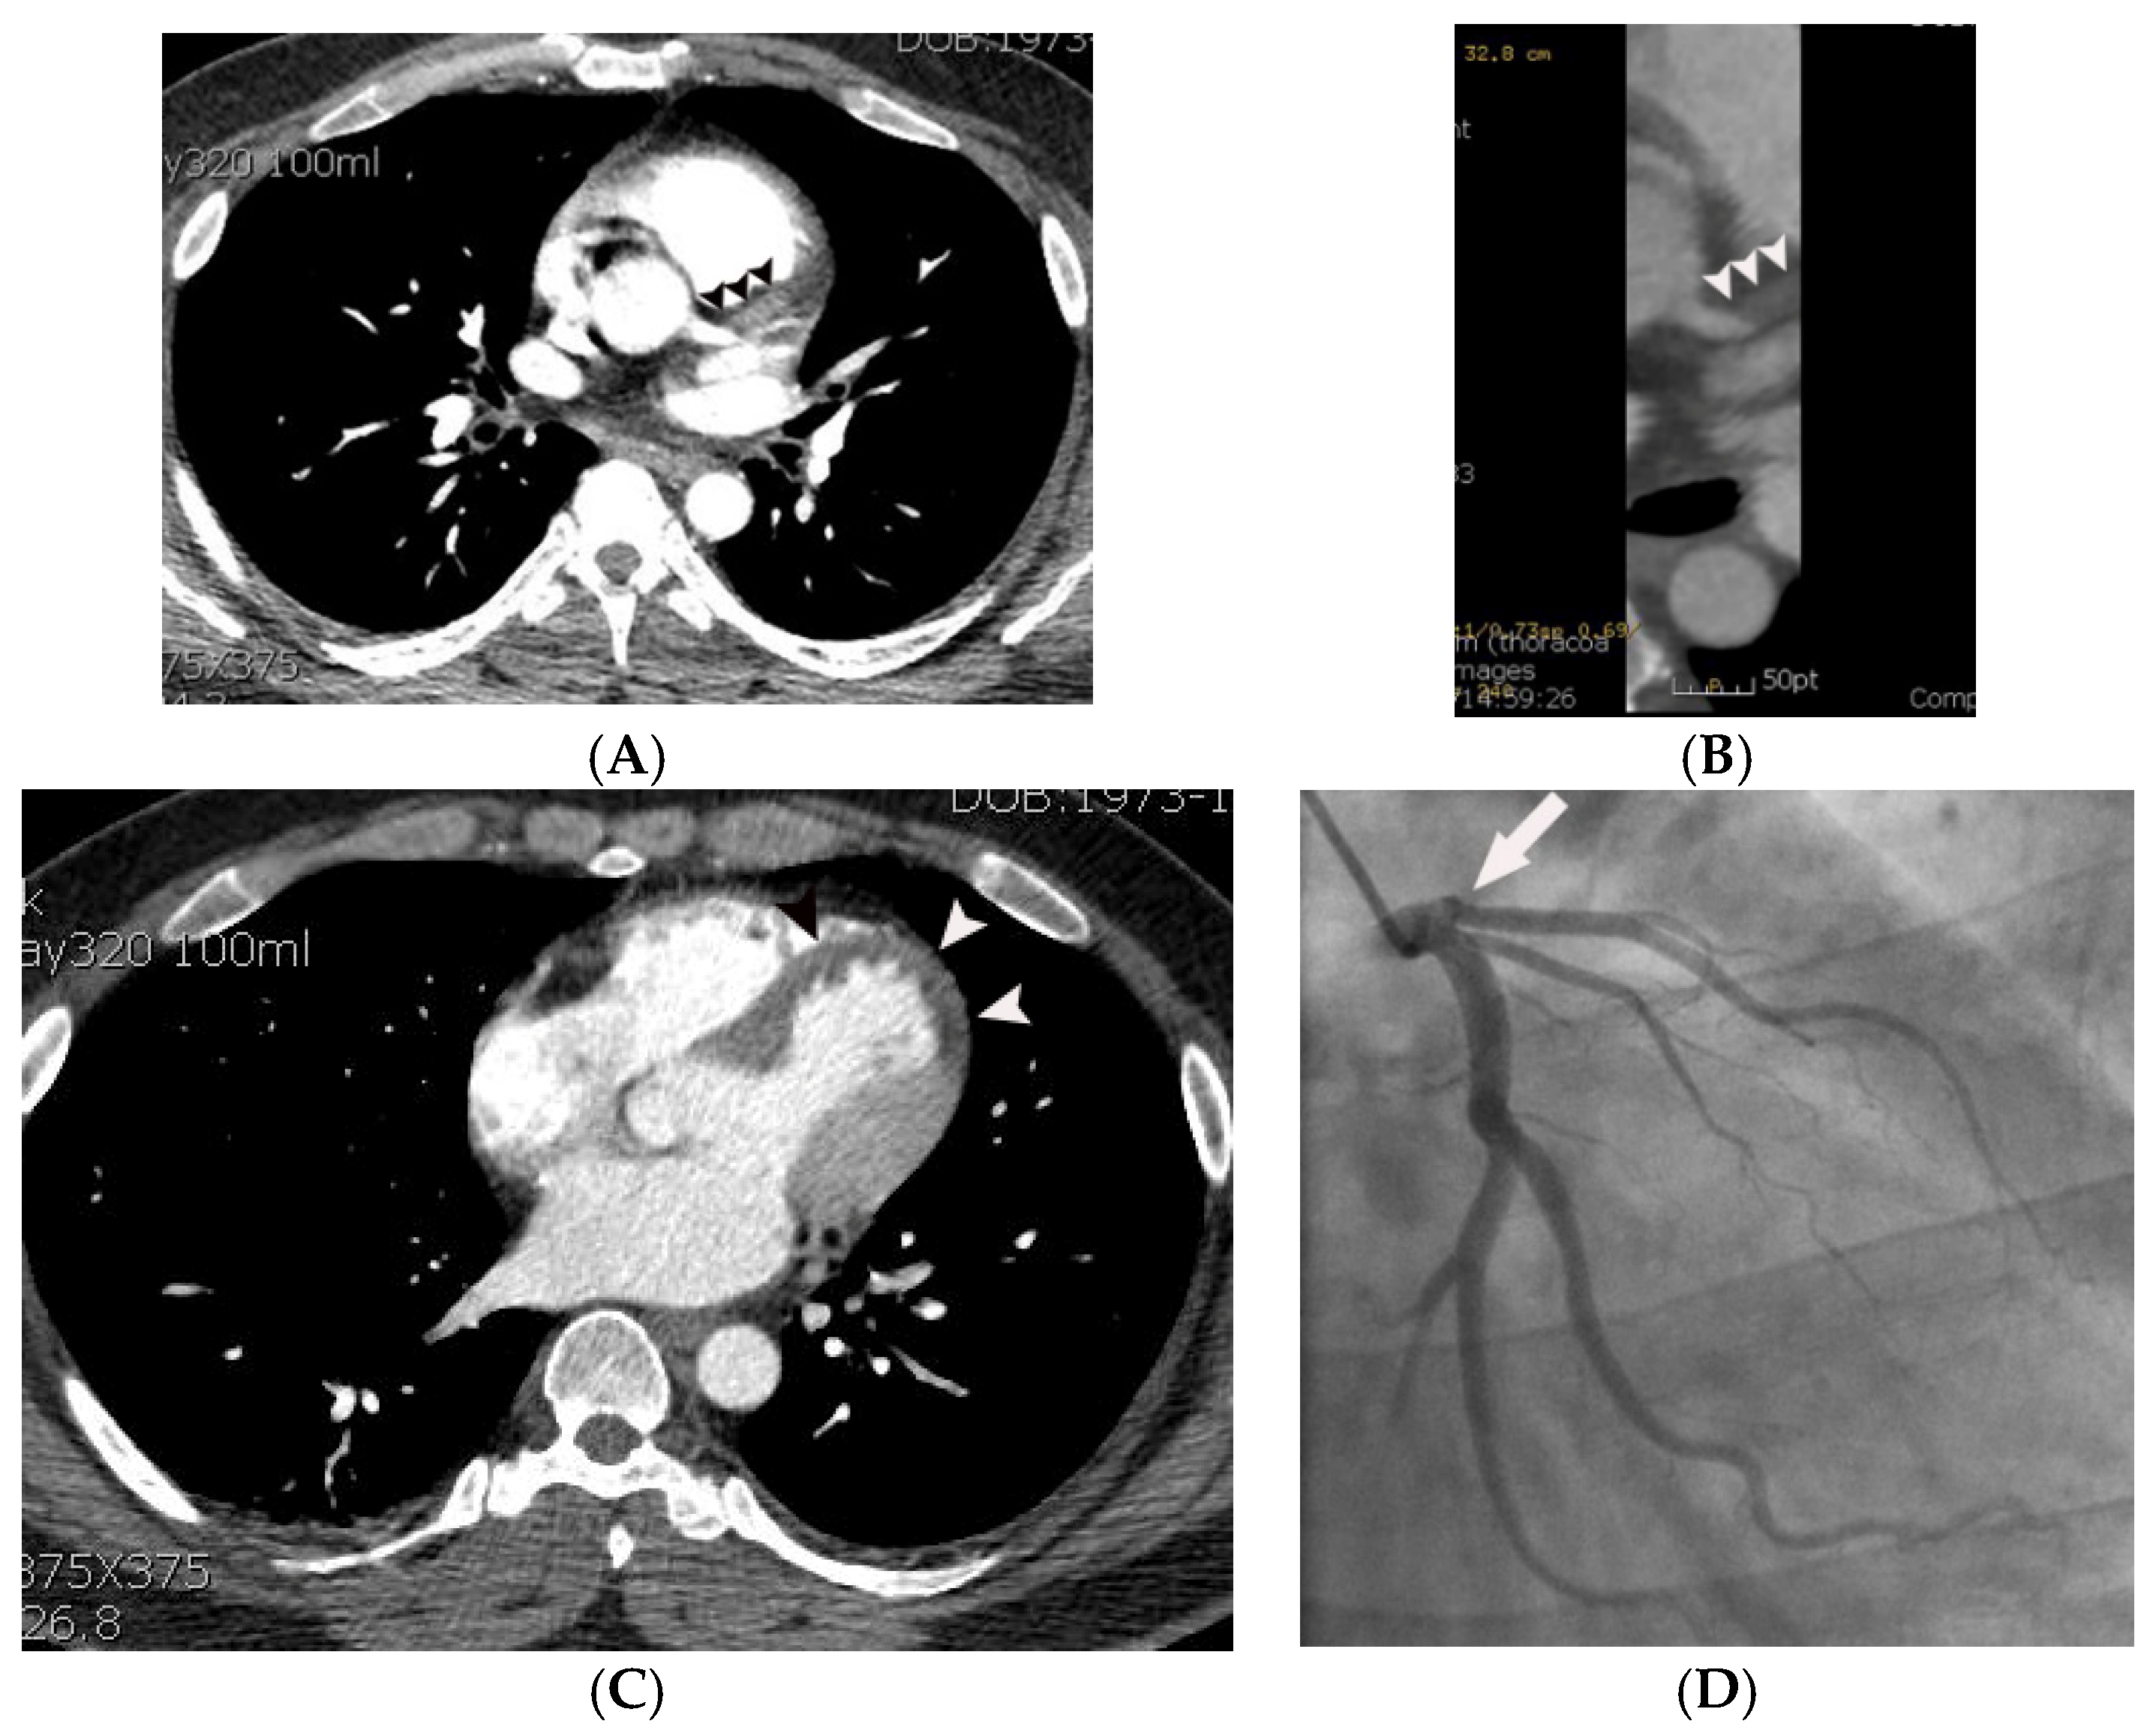

Figure 3.

Coronary artery occlusion demonstrated on non-gated enhanced chest CT in a 44-year-old man with acute myocardial infarction. (A) An abrupt cut-off (arrowheads) of contrast was noted at the origin of the left anterior descending coronary artery on an axial image at the level of the aortic root. Note that only minimal motion artifact is present in this non ECG-gated image. (B) The same finding (arrowheads) was demonstrated more clearly on a curved multi-planar reformatted image. (C) A probable myocardial perfusion defect (CT grade 2) (arrowheads) was noted in the left ventricular apex on an axial image at the level of the left atrium. (D) Subsequent coronary angiography confirmed the CT finding (arrow).